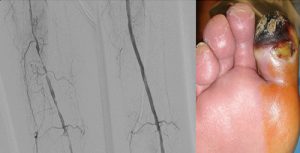

ARTERIA FEMORAL SUPERFICIAL REVASCULARIZADA MEDIANTE ATP STENT por admin | Sep 25, 2016 | 0 Comentarios Enviar comentario Cancelar la respuestaTu dirección de correo electrónico no será publicada. Los campos obligatorios están marcados con *Comentario * Nombre * Correo electrónico * Web Guarda mi nombre, correo electrónico y web en este navegador para la próxima vez que comente. Δ